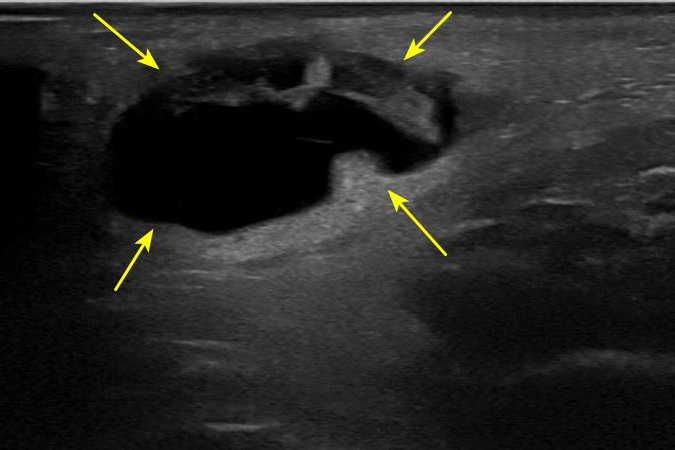

하관혈 경혈 초음파

족양명위경의 을

초음파로 관찰해보니

표준 경혈 초음파와 다르게

커다란 혈종이 보입니다.

멍 빨리 빼는 법

타박상으로 인해

혈관 밖으로 출혈이 생겨

피부 조직 밑에혈액이 고여있었던 것**이죠.